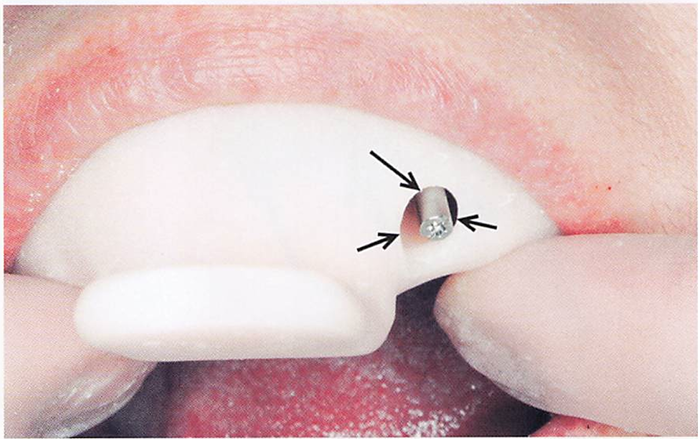

25歳の女性。前歯部の審美不良を主訴として来院した。上顎左側側切歯の欠損に対してインプラント治療を行うことになった。補綴装置の製作過程の写真を別に示す。矢印で示す開口部分の目的はどれか。1つ選べ。

a.印象材の注入

b.印象材の剥離防止

c.印象圧のコントロール

d.印象用コーピングの操作

解答を見る

d